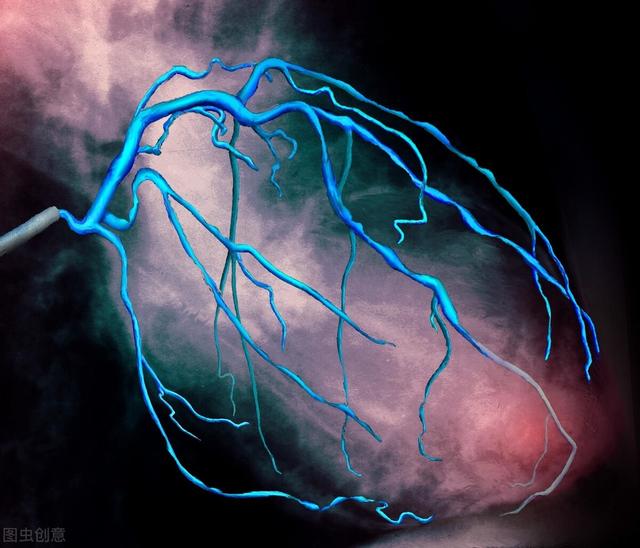

La coronarographie, en termes simples, est une ponction percutanée des artères superficielles du corps à l'aide d'un cathéter cardiaque. Celui-ci est souvent ponctionné dans l'artère radiale ou fémorale et remonte de manière rétrograde le long de l'artère pour pénétrer dans les portails de l'artère coronaire gauche ou droite, où un produit de contraste est injecté pour visualiser les artères coronaires.

En procédant de la sorte, la lumière de la principale artère coronaire gauche ou droite et de ses branches peut être clairement visualisée pour voir s'il existe des foyers sténosés dans les vaisseaux du système coronaire et pour déterminer l'étendue de la sténose. Une décision peut alors être prise quant au plan de traitement. Par exemple, une intervention, un pontage chirurgical ou un traitement médical conservateur. Ou même aucun traitement.

Il existe des angiographies coronaires et des angiographies cardiaques (auriculaires et ventriculaires). La coronarographie consiste à utiliser un cathéter fin comme un cheveu le long de l'artère radiale (au niveau du poignet) ou de l'artère fémorale (au niveau de la cuisse) pour prolonger l'entrée artificielle jusqu'à l'ouverture de l'artère coronaire du cœur, puis à injecter l'agent de contraste (dans les rayons X) dans les artères coronaires, afin de montrer la morphologie interne des artères coronaires, par exemple pour vérifier l'absence de rétrécissement des artères coronaires, de plaque, etc. L'objectif principal est de comprendre la forme interne des artères coronaires et la vitesse du flux sanguin dans les artères coronaires.